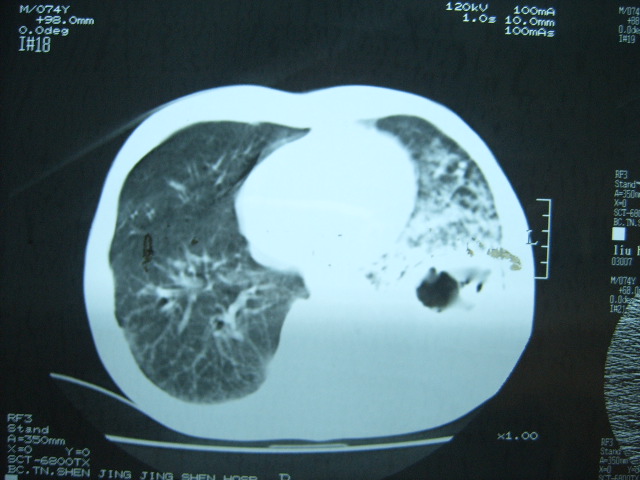

男74岁,咳嗽,寒战,低烧。有糖尿病史。

两肺结核,空洞形成,左下肺肺段隔离症待排

考虑:1、左下肺脓肿;

2、双肺结核。

考虑:糖尿病合并:1、左下肺炎继发肺脓肿;

考虑:1、左下肺脓肿;不排除霉菌感染

1、左下肺肺脓肿,合并霉菌球形成?.2、双肺陈旧性病灶.3、右上肺病灶警惕瘢痕癌,建议定期复查.

两肺结核,左下肺大片实变,内见空洞性病变,壁不规则,结合糖尿病史,考虑:结核性?霉菌性?建议结合实验室检查或治疗后复查。